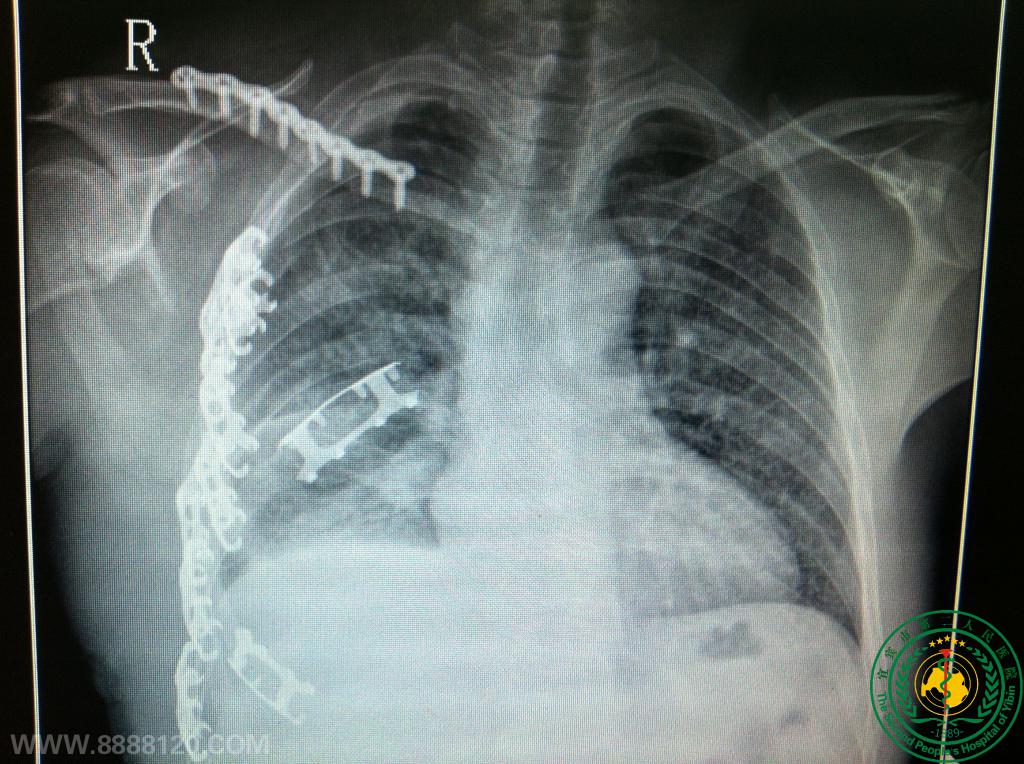

宜宾市第二人民医院胸心外科成功救治一名右肺上下叶支气管完全断裂重伤员(右上叶支气管发育异常)

宜宾市第二人民医院胸心外科成功救治一名右肺上下叶支气管完全断裂重伤员(右上叶支气管发育异常)6178